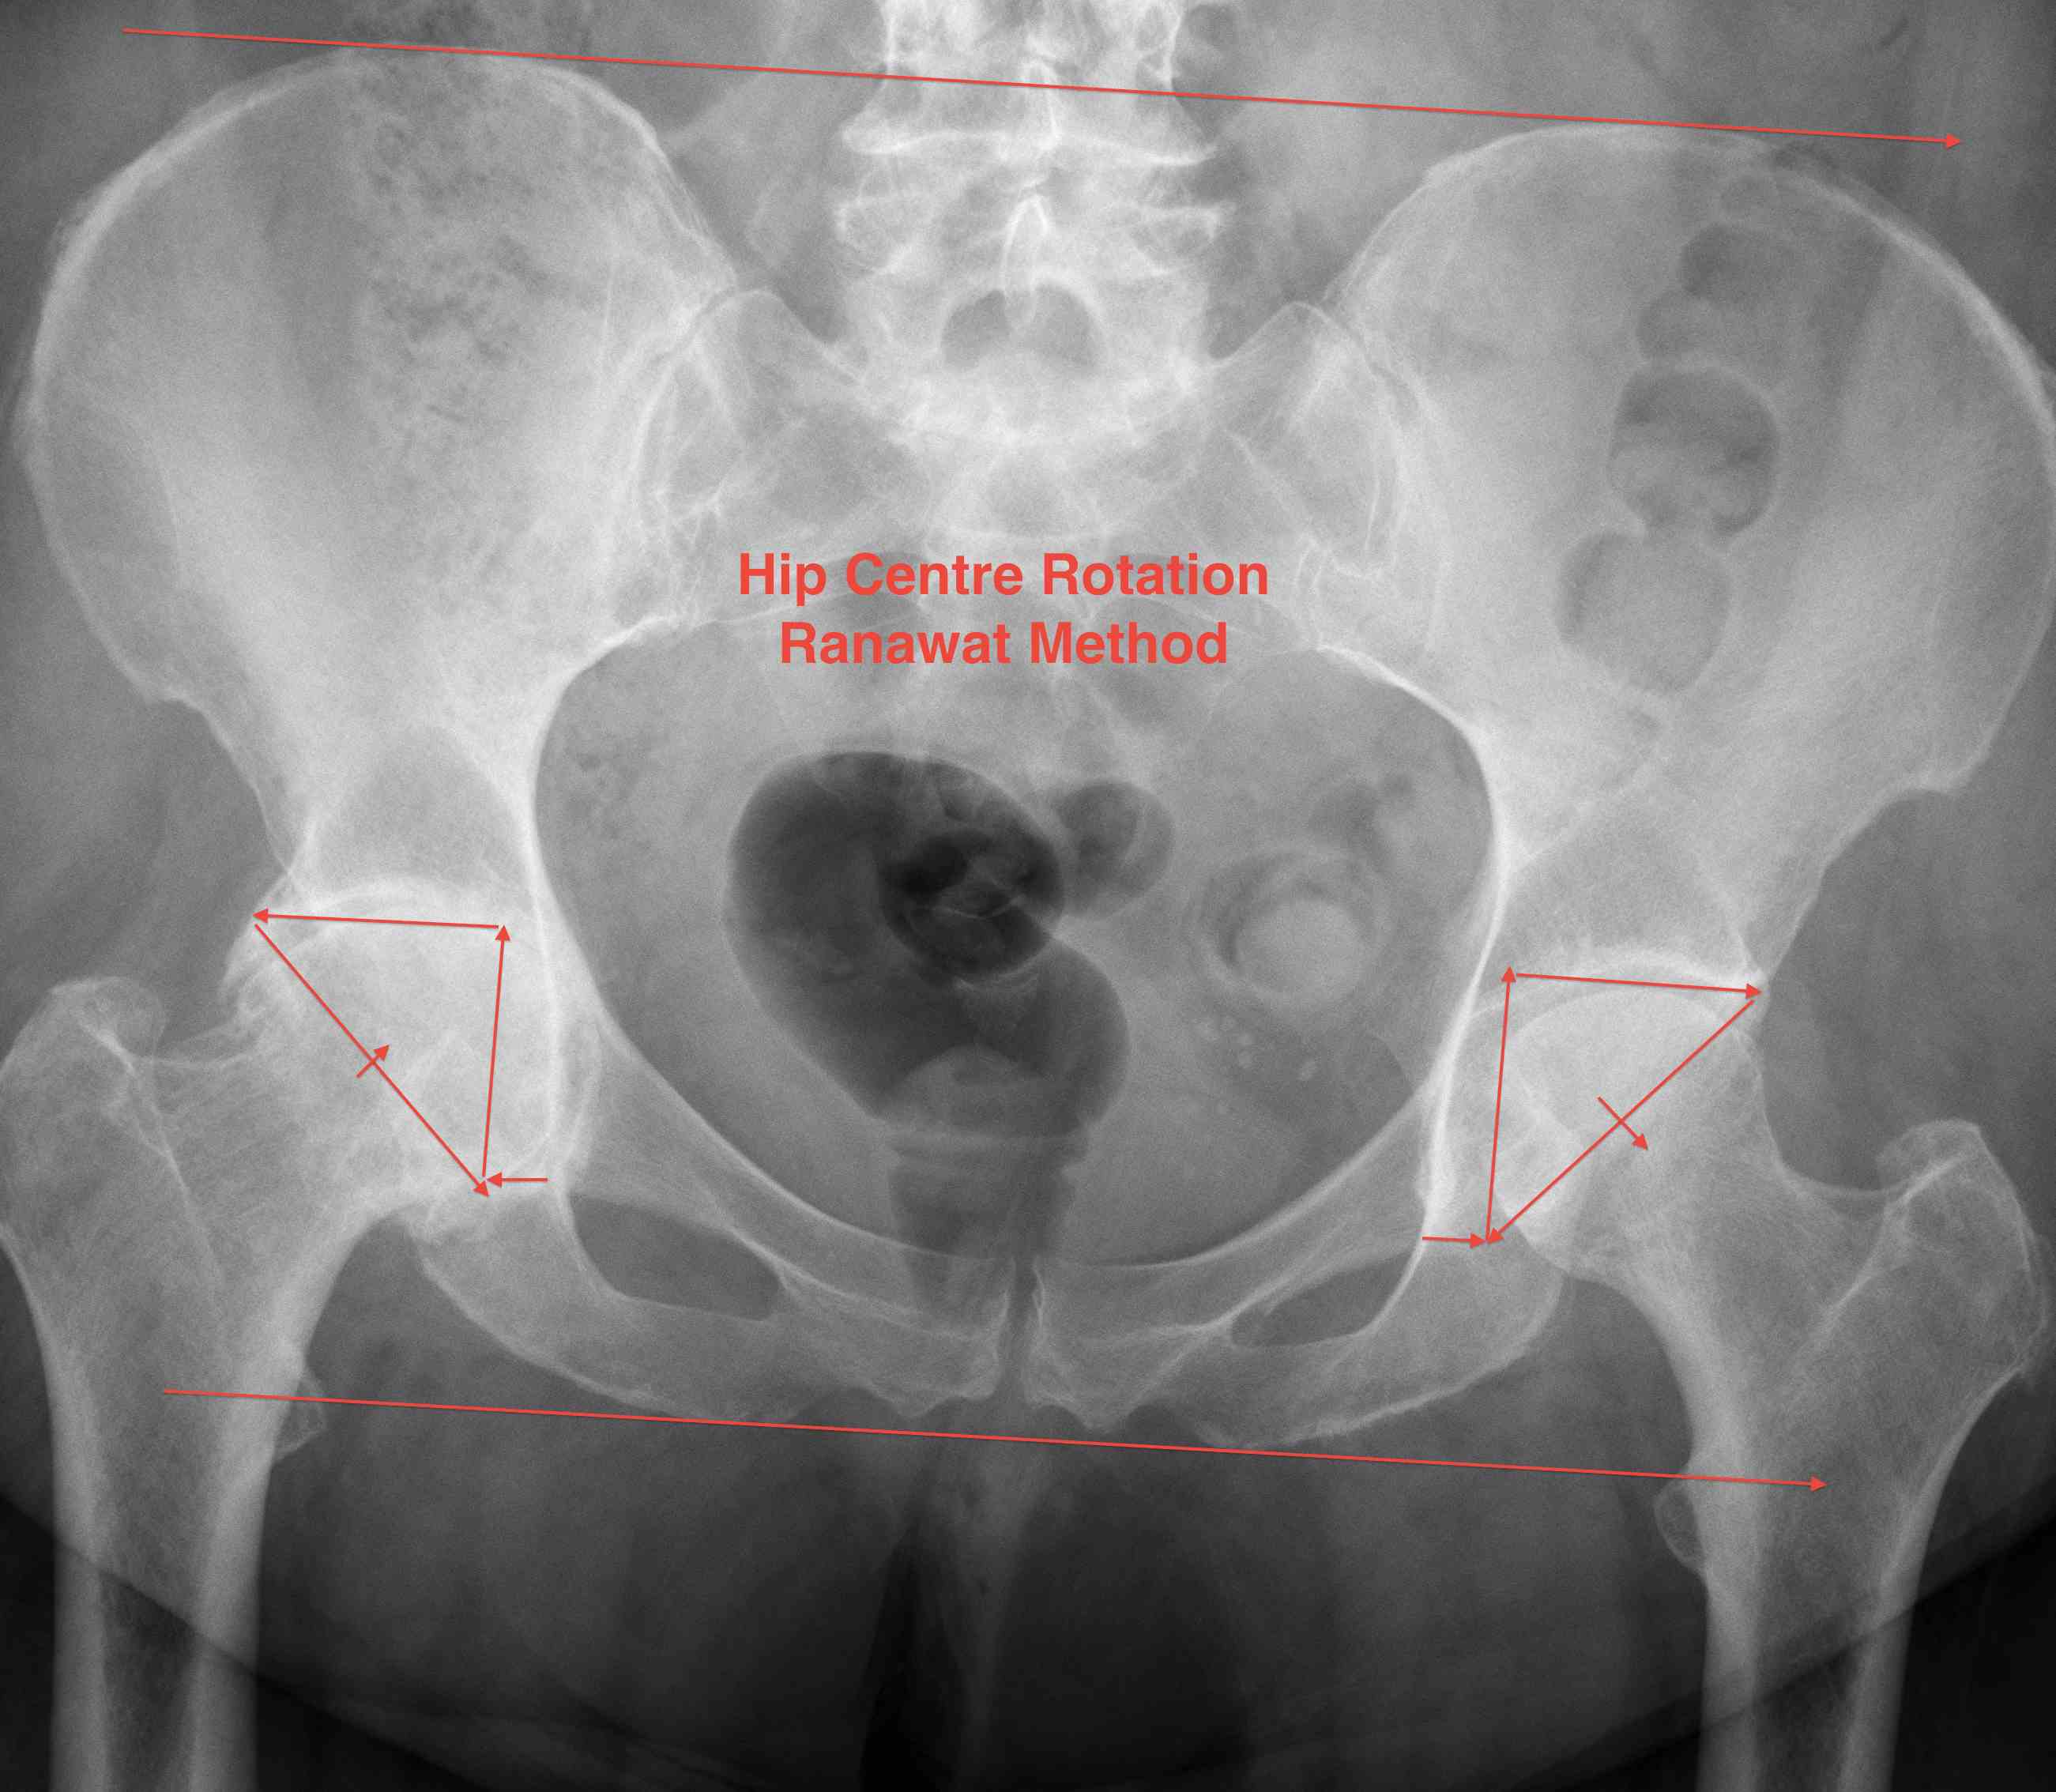

2. Ranawat Method

- draw parallel horizontal lines at the levels of the iliac crests and ischial tuberosity and mark 3 points

- Point 1: 5mm lateral to intersection of Shenton's and Kohler's lines

- Point 2: located superior to point 1 by a distance 1/5 of the pelvic height

- Point 3: similar distance horizontally from vertical line

- Isosceles triangle between 1/2/3 locates the acetabulum: line 2/3 through subchondral bone